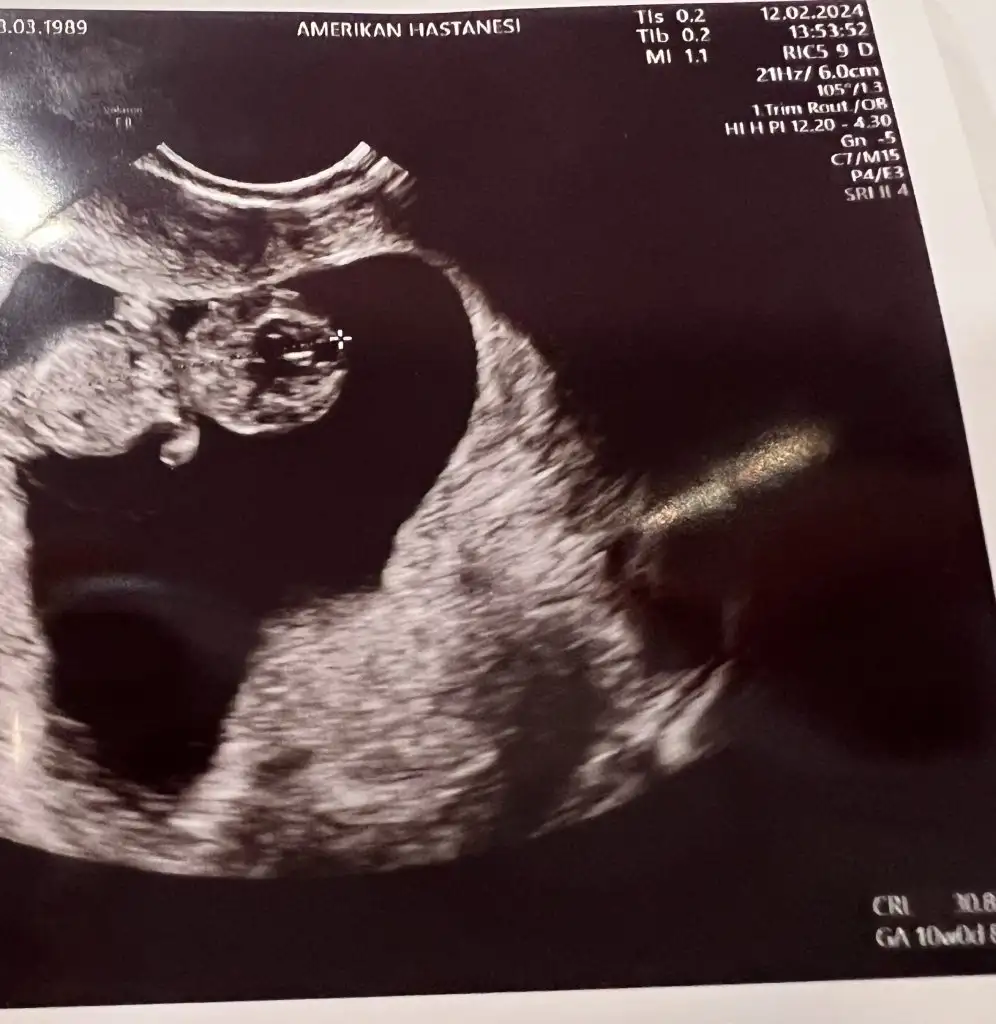

Ay o kadar mutlu oldum ki allah sağlıkla kavuştursuz siziArkadaşlar merhaba bebeğimin kalbi gümbür gümbür şükürler olsun. Ufak Bi kanama alanı var ama problem yaratmaz dedi. Doktor bana dedi ki beni 5 yıllık depresyondan çıkarttın dedi.Önce keseyi göremedik uzun süre sonra lekelenme sonra kanama derken. gebelik belirtilerim kayboldu şimdi Bi şey olmaz sa daha olmaz dedim. Doktor dedi ki bana bu bebek umudu aşıladı bana adı umut olsun dedi

Kız bu ne minik kaplumbağaÇok sevindim canımBenimde 10+5 oldu, en son gecen hafta gittiğimde bebegı cok begendı 3-4 gun onden gıdıyormus.

Yaa tali kaç haftalıksın kuzumArkadaşlar merhaba bebeğimin kalbi gümbür gümbür şükürler olsun. Ufak Bi kanama alanı var ama problem yaratmaz dedi. Doktor bana dedi ki beni 5 yıllık depresyondan çıkarttın dedi.Önce keseyi göremedik uzun süre sonra lekelenme sonra kanama derken. gebelik belirtilerim kayboldu şimdi Bi şey olmaz sa daha olmaz dedim. Doktor dedi ki bana bu bebek umudu aşıladı bana adı umut olsun dedi

8 haftalık canımYaa tali kaç haftalıksın kuzum